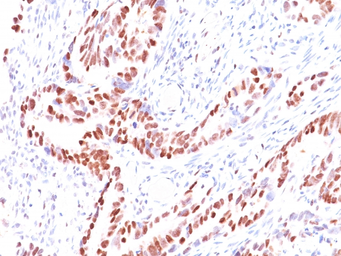

GTX34941 IHC-P Image

IHC-P analysis of human prostate carcinoma tissue using GTX34941 p57 Kip2 antibody [KIP2/880].